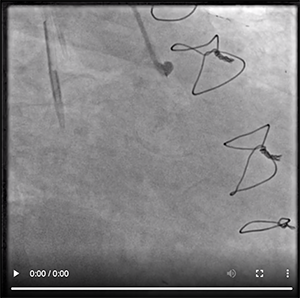

Because the aortic arch was mildly calcified and only mildly tortuous, we were able to negotiate the left subclavian artery with relative ease using a 0.035-inch angled Glidewire Advantage guidewire (Figure 1). Because the patient developed spasm, we chose not to exchange to another catheter and used the JR 4 catheter for the native right coronary artery (Figure 2) and all the grafts, including the LIMA. There was clear diffuse disease progression in the native LAD artery. We discussed intensifying medical therapy and more aggressive dialysis to stabilize her LV function, but we decided against it due to changes in the electrocardiogram and spasm. Video 1 and Video 2 reveal the anatomy defined during catheterization. Video 3, Video 4, and Video 5 illustrate how we negotiated the left subclavian artery and the subselective LIMA angiogram.